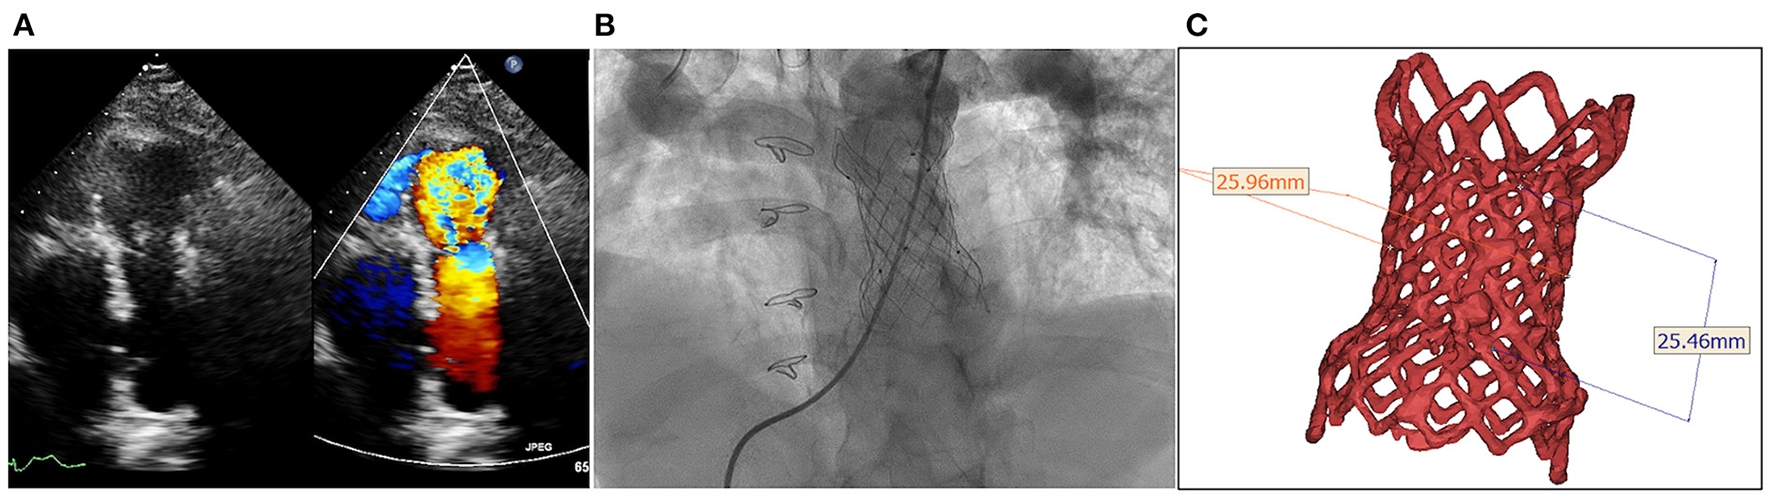

A 54-year-old female with a history of TOF was admitted to our hospital with complains of exertional dyspnea and chest distress. She underwent surgery for TOF with transannular patching of right ventricular outflow tract (RVOT) at the age of 18. Five years ago, she received TPVI, using a P26-25 mm (diameter-length) self-expandable Venus P-valve (Venus Medtech, Hangzhou, China) due to severe pulmonary regurgitation with right heart enlargement. Unfortunately, bioprosthesis-associated IE occurred due to dental caries 6 months after TPVI. Transthoracic echocardiography (TTE) showed vegetation attached on the prosthetic valve and blood culture indicated streptococcus viridians. At the end of 6 weeks of intravenous penicillin and gentamycin, her blood cultures sterilized, her vegetation size was reduced, and she achieved prosthesis functional recovery (6). Then, she received dental caries extraction under antibiotic prophylaxis with intravenous penicillin 80 million units/day for 3 days. During close follow-up, she had not got relapse of IE. However, dysfunctional bioprosthesis was still detected by TTE with thicken leaflet, severe pulmonary regurgitation 3 years later (Figure 1A; Supplementary Video 1), moderate to severe tricuspid insufficiency and right heart dilation. Considering the relatively low risk of procedural complications, a decision of valve-in-valve TPVI with a self-expandable valve was made.

Figure 1

Degenerated bioprosthesis with complete frame. (A) Transthoracic echocardiography shows severe pulmonary regurgitation; (B) Angiography reveals severe pulmonary insufficiency; (C) The annular size calculated on computed tomography.

The procedure was performed with fluoroscopic and TTE guidance under general anesthesia. Bilateral femoral veins were used, and right heart catheterization was first executed. Pulmonary artery pressure was 35/8 mmHg and right ventricle pressure was 50/8 mmHg. Severe pulmonary insufficiency appeared on angiography (Figure 1B; Supplementary Video 2). After pre-dilation with a 25 mm × 50 mm (diameter × length) balloon (Balt, Montmorency, France), systolic pressure gradient across the bioprosthesis decreased from 15 mmHg to 6 mmHg. Since the annular size of 25.9 mm calculated on computed tomography and three-dimension reconstruction (Figure 1C), a P28-25 mm (diameter-length) self-expandable Venus P-valve (Venus Medtech, Hangzhou, China) with 22-F delivery system was planned to be deployed. The process was beset with difficulties in advancing the delivery sheath. The buddy wire technique, which was employed with two Lunderquist wires, was attempted but the delivery system still failed to be advanced and positioned appropriately. Finally, the 14-F Cook sheath (Cook Medical, Bloomington, USA) was advanced over the second Lunderquist wire, which passed through the RVOT and placed in the distal of right pulmonary artery. The 14-F Cook sheath served as modified buddy wire providing extra support and straightening the vessel and the RVOT (Figure 2A). Maneuvering the 22-F Venus P delivery system alongside the 14-F Cook sheath aided in the advancement of the delivery system into the proximal end of left pulmonary. Prior to the deployment of the second pulmonary valve, the 14-F Cook sheath was pulled back into inferior vena cava. The new self-expanding valve was then successfully delivered (Figure 2B) and implanted. Post-dilation with a 25 mm × 50 mm (diameter × length) balloon (Balt, Montmorency, France) was performed to better shape for the stent strut and RVOT. Post-procedure angiography and TTE showed no pulmonary regurgitation (Figures 2C,D, 3; Supplementary Videos 3, 4). Then pulmonary pressure was raised to 35/18 mmHg.